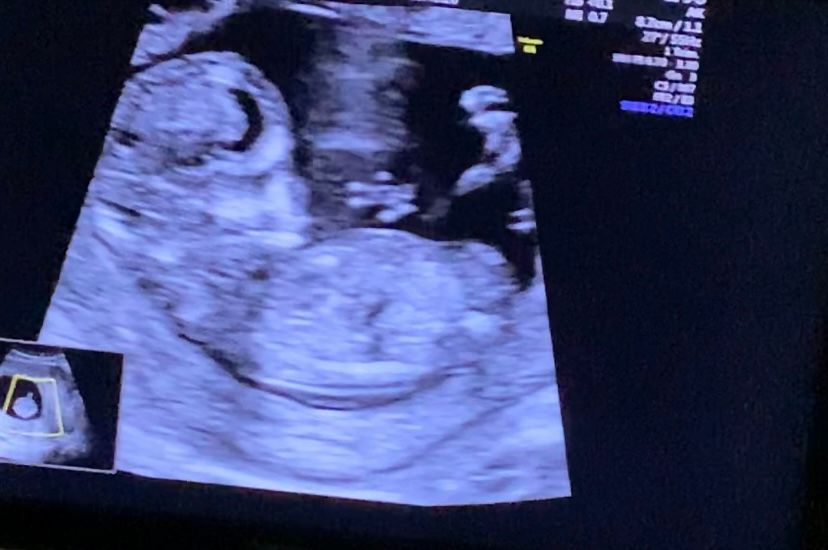

Девочки , мальчик или девочка?

12 Недель , сказали половой бугорок кверху , посмотрите пожалуйста :)

😂😂😂 мне кажется, на последнем фото в уголке фигура из 3х пальцев . Вообще кверху парень, а девочка- он параллелен тельцу. Но это же опять из теории и прочитанного.